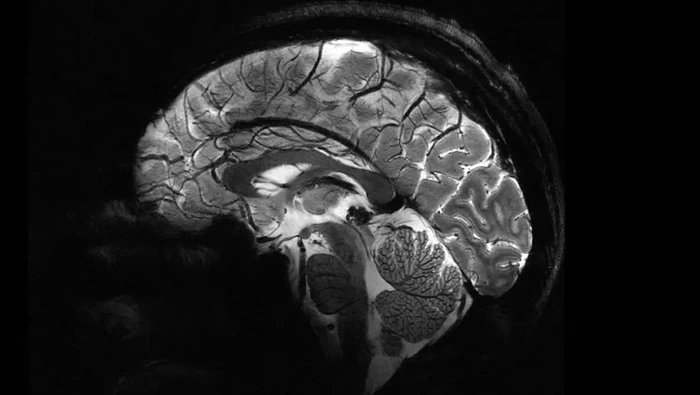

Alat MRI paling canggih di dunia memungkinkan peneliti untuk melihat detail otak manusia. Hasil pemindaiannya mencapai tingkat presisi baru yang memberikan pencerahan pada misteri tentang otak dan penyakit yang menghantuinya.

Medan magnet yang diciptakan oleh MRI tercanggih ini adalah sebesar 11,7 tesla, sebuah unit pengukuran yang dinamai menurut penemu Nikola Tesla. Di layar komputer, peneliti membandingkan gambar yang diambil oleh pemindai yang dijuluki Iseult ini, dengan gambar dari MRI normal.

"Dengan mesin ini, kita bisa melihat pembuluh darah kecil yang memberi makan korteks serebral, atau detail otak kecil yang selama ini hampir tidak terlihat," ujar Alexandre Vignaud, fisikawan dari France's Atomic Energy Commission (CEA) yang terlibat dalam proyek tersebut dikutip dari SCMP.